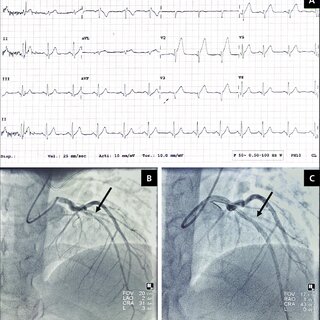

변이형 협심증 진단

우선 의사의 증상과 병력, 위험요인등을 문진한뒤 EKG(심전도검사), 관상동맥조영술, 심장에 부하를 주는 테스트, 혈액검사 등으로 진단을 하게 됩니다.

보통은 외과적인 수술은 시행하진 않지만 약물 치료과 전혀 효과가 없거나, 혈관 경련 및 수축이 심하여 위독한 경우 관상동맥 우회술이나 스텐트 삽입등의 수술을 하는 경우도 존재합니다.